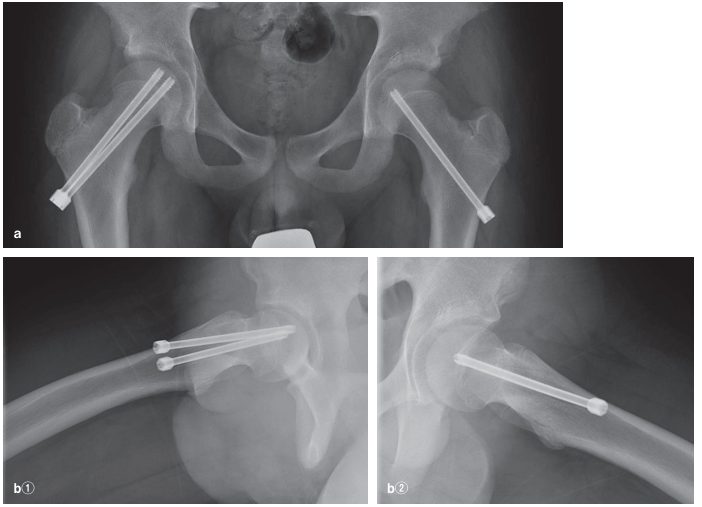

大腿骨頭すべり症は、大腿骨頭に圧(体重)がかかり、骨端線部で骨端が後下方にすべるように発症する疾患です。10-14歳に発症し、11歳前後の男児に好発します。病型分類として明らかな外傷を契機として発症する急性型、明らかな外傷歴はなく徐々に発症する慢性型が存在し、慢性型が全体の70〜80%を占めています。慢性型の経過中に軽微な外傷で急にすべりが増強することがあります。

診察とレントゲンなどで診断します。仰臥位で患肢を屈曲すると患肢が開排(外転・外旋)していくドレーマン徴候を呈します。

単純X線正面像で骨端線が不鮮明にみえます。すべりが進行すると骨端が内側に位置するTrethowan(トレソーワン)徴候、側面像では骨端核後方部分が寛骨臼の外にはみ出すCapener(ケイプナー)徴候を認めます。

診断後はただちに荷重を禁止(松葉杖もしくは車いす)します。病型とすべりの進行度により決定されます。急性型では、牽引あるいは徒手整復で転位した骨端核をできるだけ正常の位置に整復してから内固定を行います。慢性型では、すべりの程度が軽度の症例は整復せずにその位置で固定を行います。すべりの程度が高度な症例には、各種の骨切り術を施行しすべりの角度を矯正します。